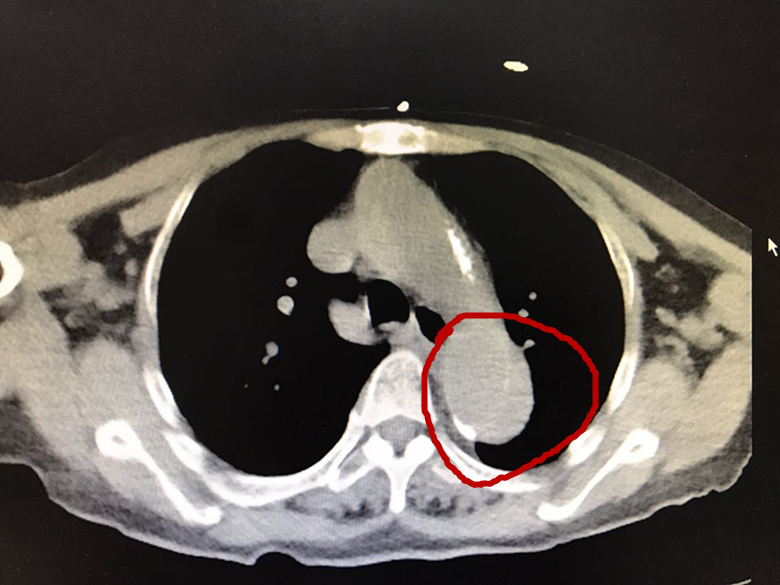

事情总是朝坏的方向发展,放射科打来电话报告危急值:主动脉夹层A型!下面就是患者CT中的截图,红色圈中的便是主动脉,因为这是普通CT平扫,所以有可能显示不清,如果仔细观看的话,就会发现主动脉内已经分为真腔和假腔!

主动脉夹层指的是主动脉腔内的血液从主动脉内膜撕裂口进入主动脉中膜,并沿着主动脉长轴方向扩展,导致主动脉真假两腔分离的一种病理改变。而这位没有明显症状的老人,夹层是起源于升主动脉,已经扩展超过主动脉弓到降主动脉。